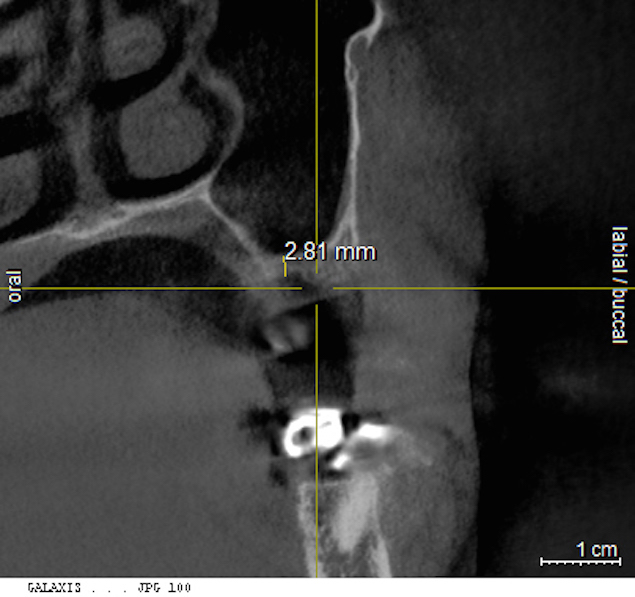

The pretreatment radiograph suggesting more than 2 mm of subantral alveolar bone.

Figure 21

Cross-sectional view of the edentulous site demonstrating minimal bone height below the sinus floor.

Figure 22

A patient who had received treatment 10 years ago for implants in the mandibular arch said her general dentist wanted to place an implant in site No. 3, using a hammer. Although that clinician believed the site had sufficient bone based on a periapical x-ray findings (Figure 21), the findings from a cross-sectional computed tomography scan helped determine that she had less than 3 mm of bone in the ridge (Figure 22). Froum et al14 and Tarnow et al15 both demonstrated the efficacy of combining rhBMP-2/ACS with mineralized bone allograft in sinus graft procedures. Marx et al16 demonstrated the combination of this growth factor with mineralized allograft and PRP to reconstruct severe maxillary defects. Given the 4 mm of minimal requirement for simultaneous implant placement, the author performed a lateral window sinus graft. An absorbable collagen sponge hydrated with rhBMP-2 was combined with mineralized bone allograft and used to obturate the site after reflection of the Schneiderian membrane along the medial sinus wall. A portion of the rhBMP-2/ACS was adapted over the grafted window osteotomy (Figure 23). After healing for approximately 5 months, the patient received a computer-guided implant surgery (Figure 24). The implant was restored with a screw-retained crown after a healing period of approximately 3 months.